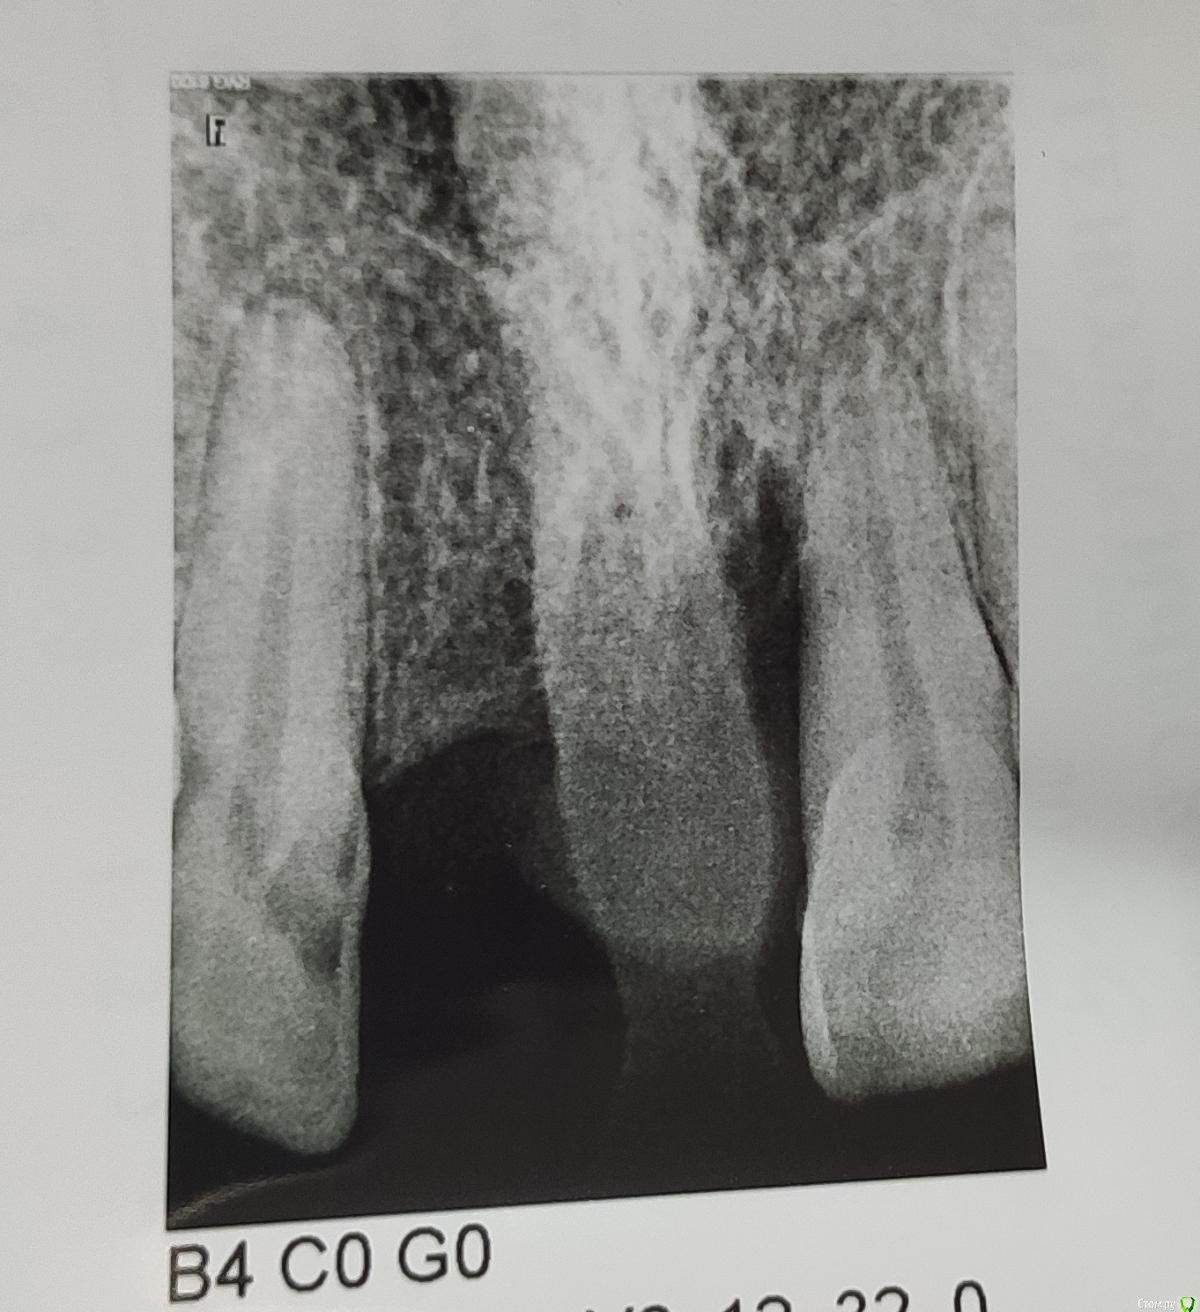

andrewV Опубликовано 30 января, 2020 Поделиться Опубликовано 30 января, 2020 (изменено) Добрый вечер. 20 лет назад удалили передний верхний зуб, все это время ходил со съемный протезом. Решил сходить провериться, сказали все очень плохо, надо удалять соседние зубы. Что можно сделать в моем случае, реально ли сохранить соседние зубы? Снимки прикладываю. Изменено 30 января, 2020 пользователем andrewV Ссылка на комментарий

DmitrySH Опубликовано 30 января, 2020 Поделиться Опубликовано 30 января, 2020 Зуб 21. удалять из-за большой потери кости. Зуб 12. сложно сказать, вижу кариес корня. Но непонятно насколько глубоко 2 Ссылка на комментарий

andrewV Опубликовано 3 марта, 2020 Автор Поделиться Опубликовано 3 марта, 2020 (изменено) В одной из клиник предложили удалить единичку с кистой и обточить двойки под коронки, на них же можно будет повесть временный протез, пока будут приживаться импланты и костная ткань. Можно ли как-то обойтись без обточки, но не ходить 3-4 месяца без передних зубов? Почему-то ничего не сказали насчет кариеса корня на двойке, его же надо депульпировать в таком состоянии? Изменено 3 марта, 2020 пользователем andrewV Ссылка на комментарий